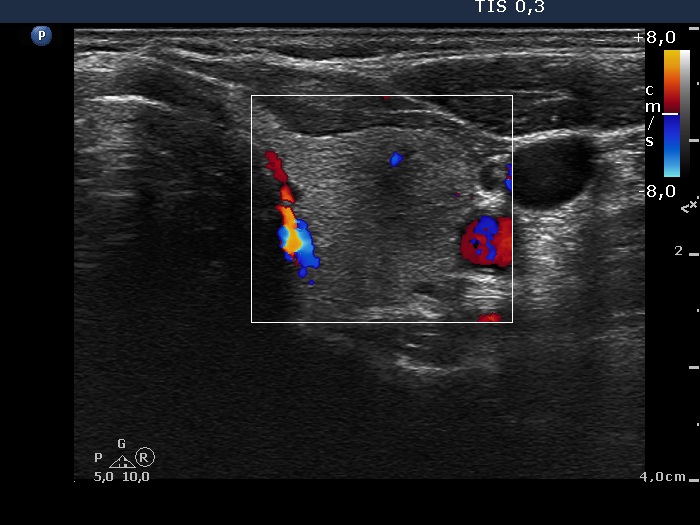

Left lobe, transverse scan, color Doppler mode. The vascularity is scanty.